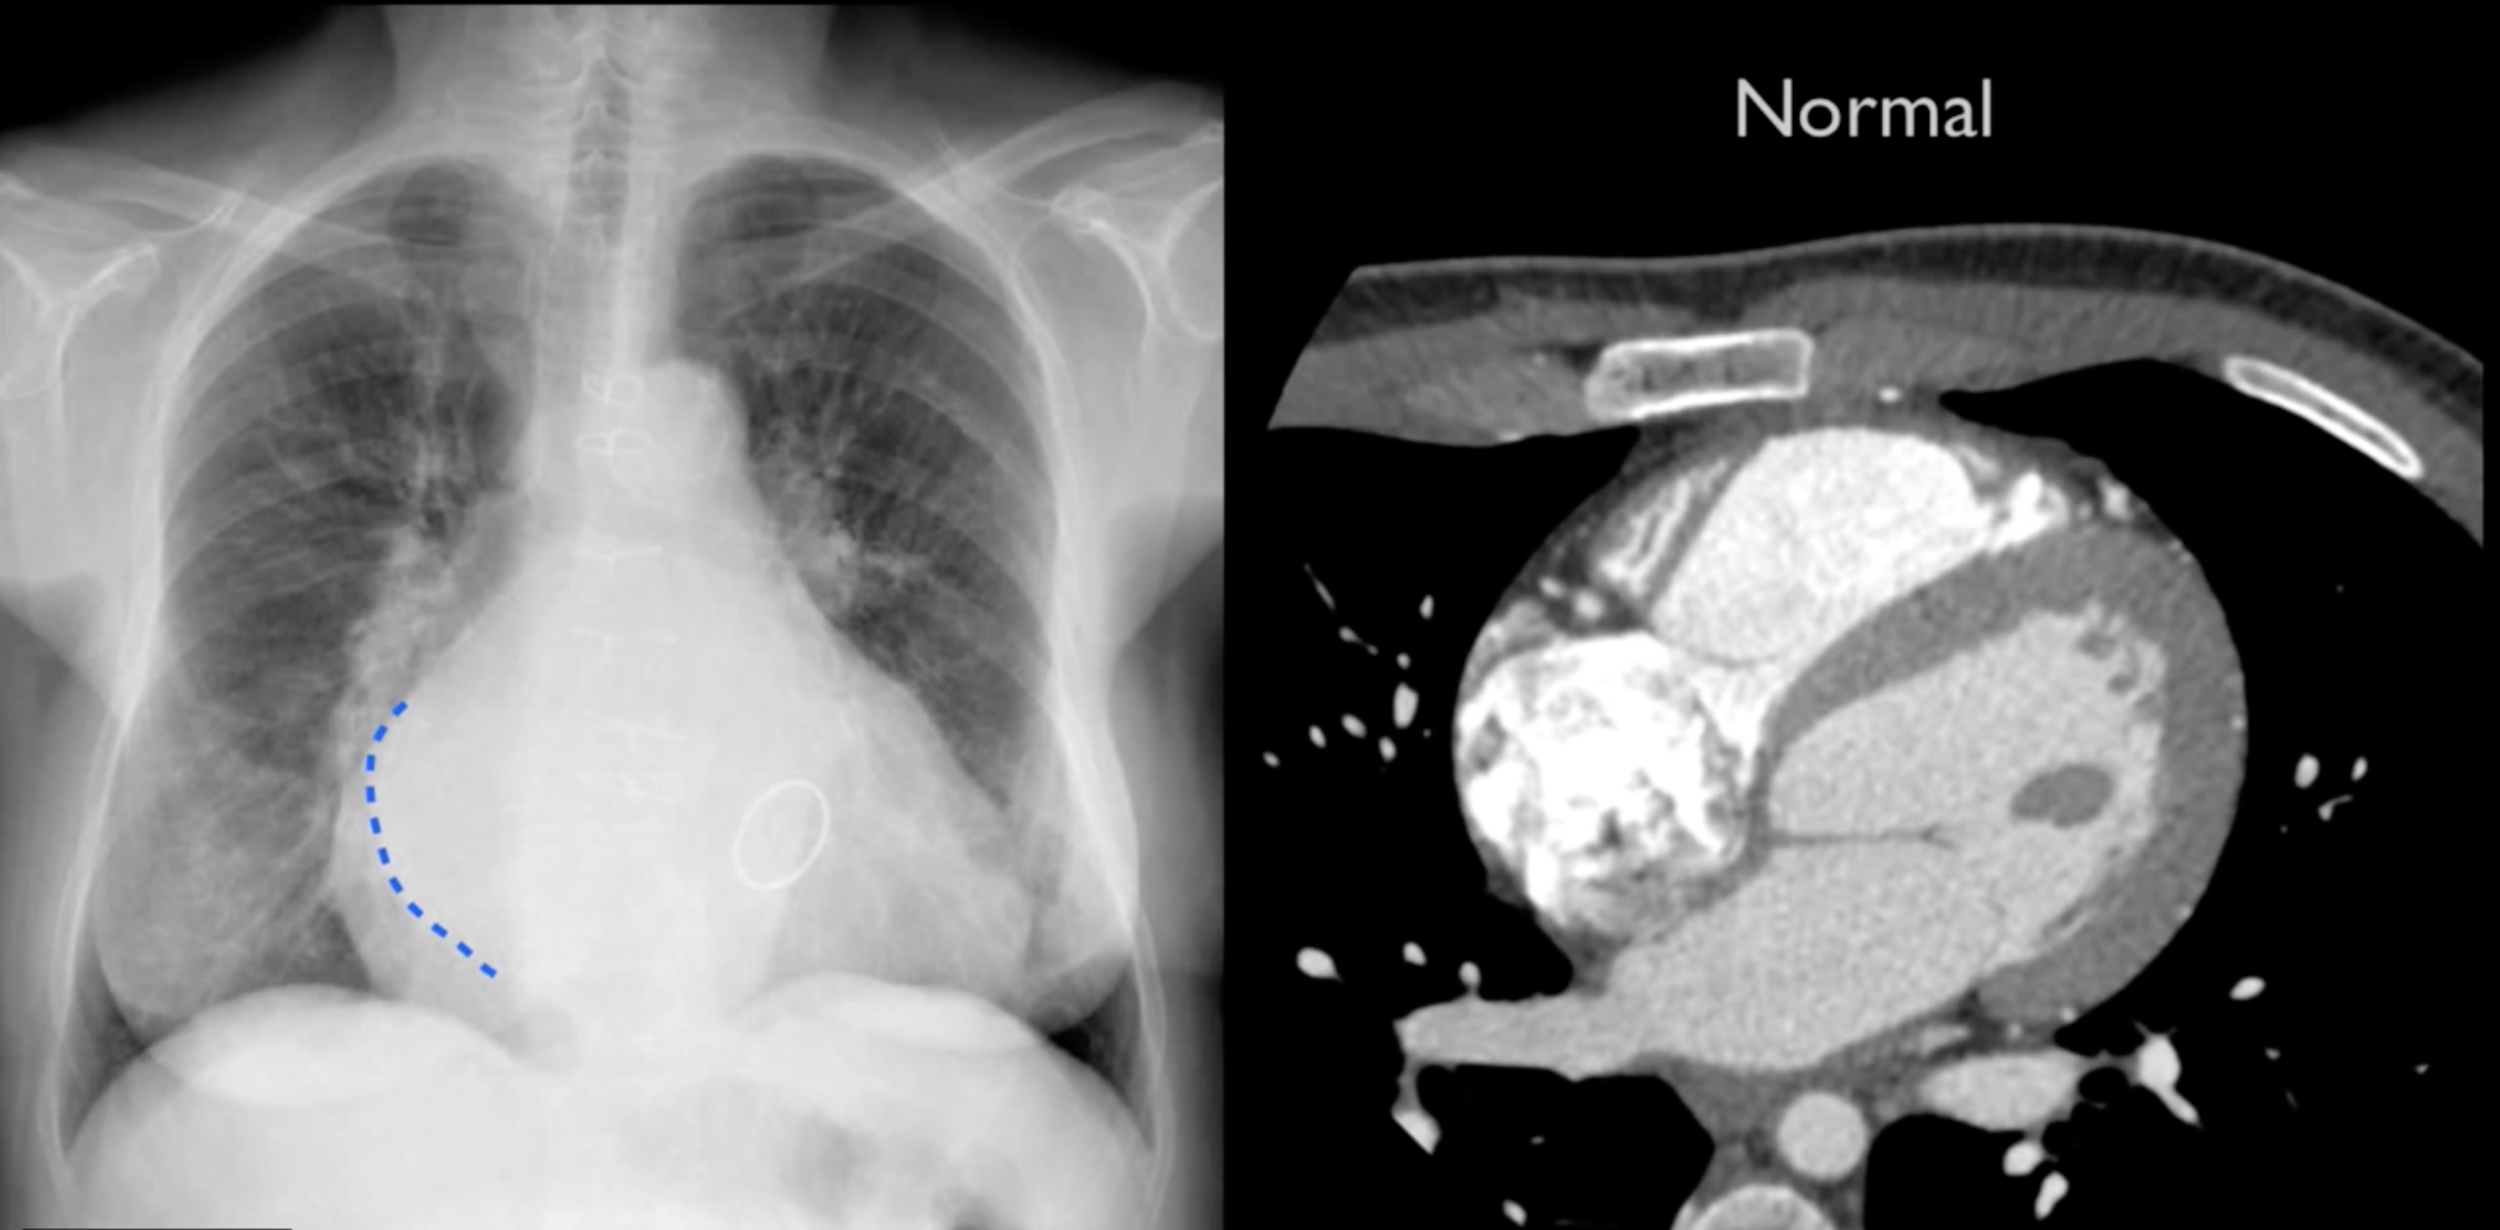

Left Atrial Enlargment

Bonus Points: 75M Chest PainĀ